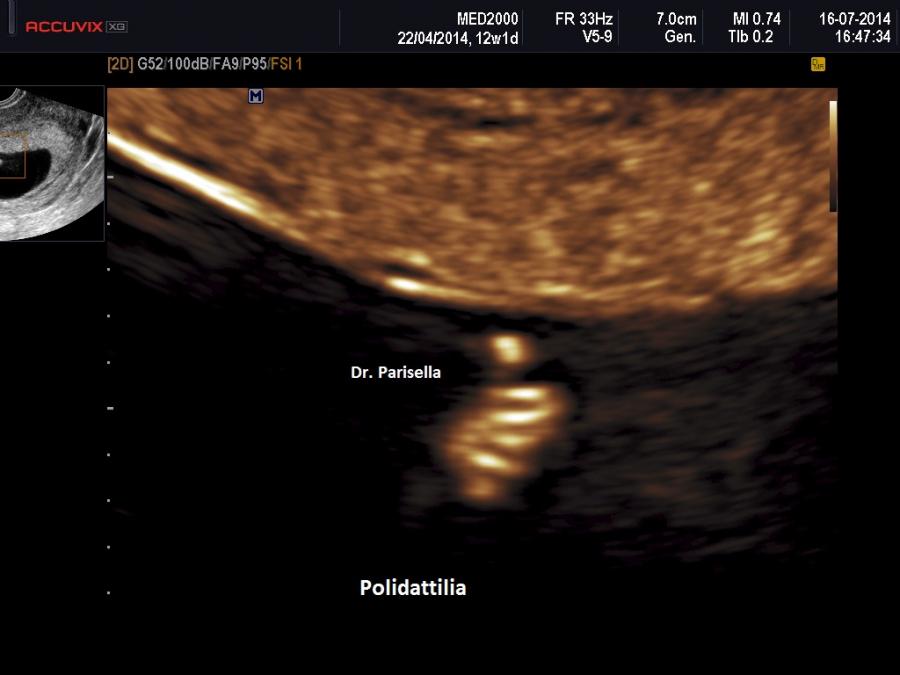

Le lesioni caratteristiche a carico del SNC sono rappresentate  da idrocefalo grave, con ventricoli aperti nello spazio subaracnoideo, ipoplasia cerebrale, anomalie della linea mediana e del setto pellucido (agenesia del corpo calloso); possono essere presenti encefalocele occipitale, una caratteristica conformazione del forame magno “key-hole shaped”, mandibola piccola e naso malformato, labio-palatoschisi. Caratteristica è la polidattilia postassiale alle mani e preassiale ai piedi (l'alluce duplice è altamente caratteristico, quasi esclusivo, di questa condizione morbosa). Segnalati anche piede torto e difetti cardiovascolari (difetti del setto atriale; atrio unico). Come ha segnalato lo studio di Salonen e coll. (1981) condotto su 28 neonati di 18 famiglie, l'esito abituale della gravidanza è la nascita di feto morto o morte in epoca neonatale.

La Diagnosi Prenatale si basa su: 1) assenza di movimenti attivi fetali; 2) polidattilia postassiale alle mani; 3) polidattilia preassiale ai piedi;  4) idrocefalia; 5) polidramnios.